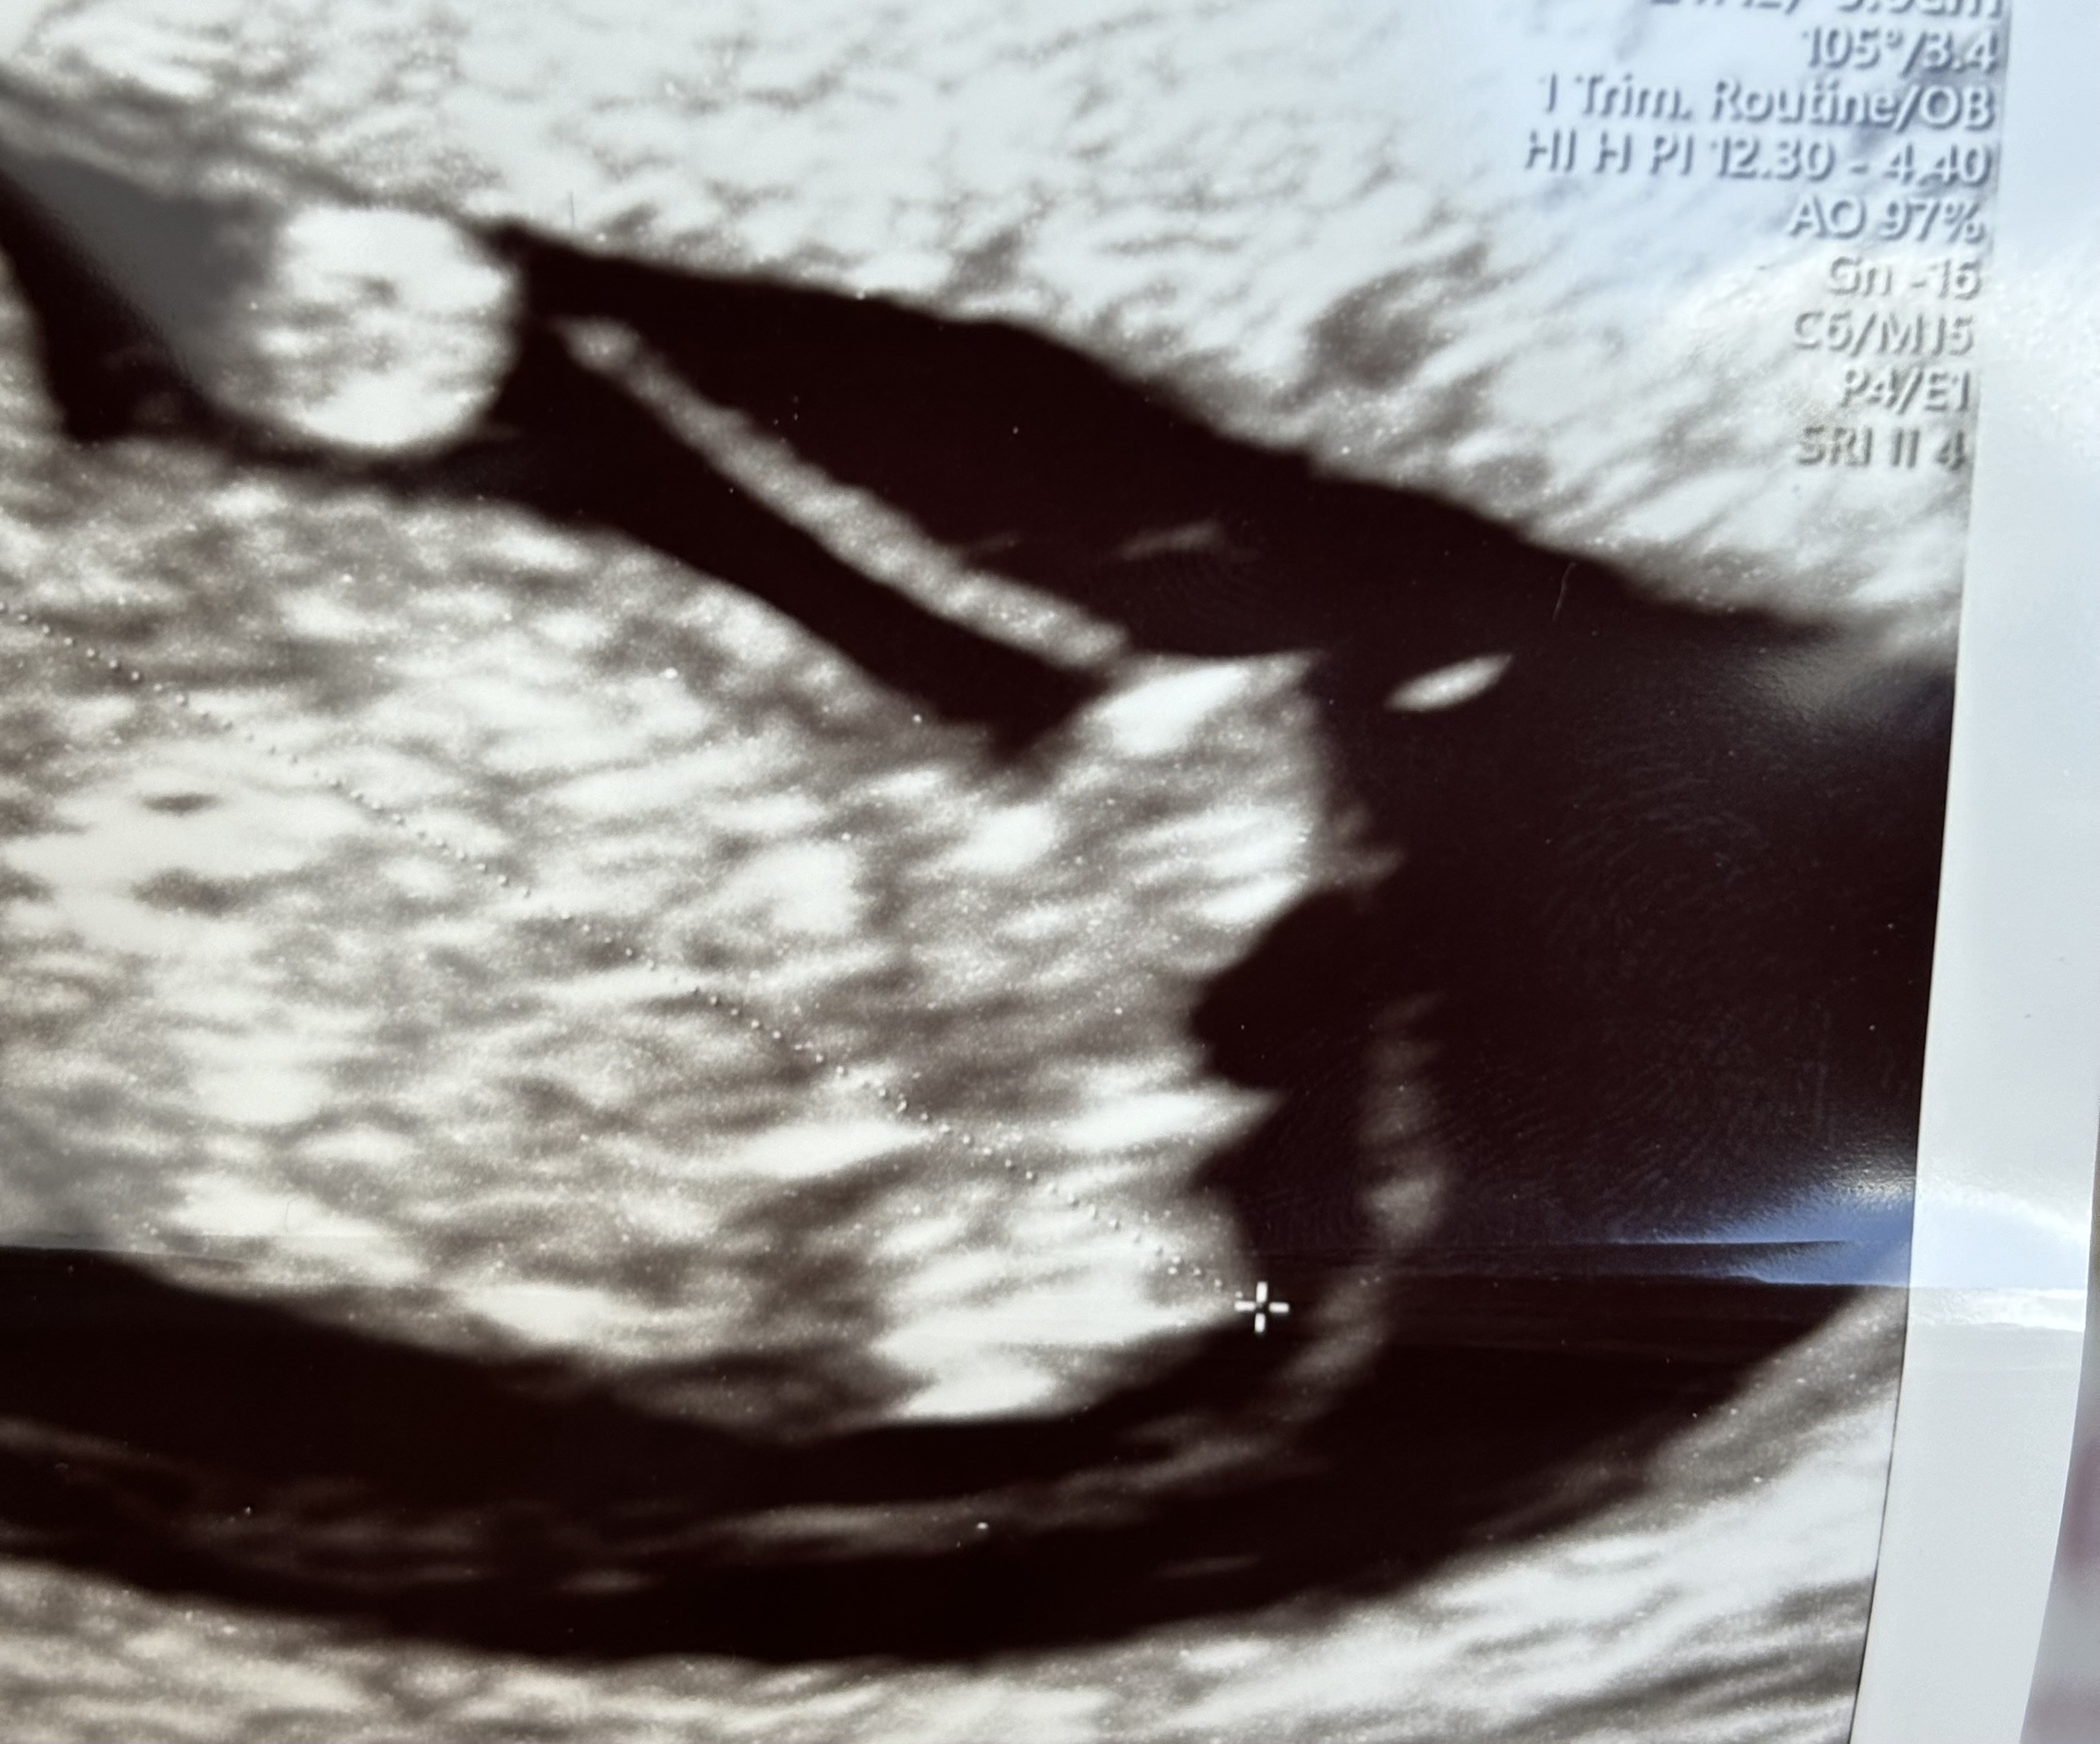

Dziewczynka na moje oko. Wyrostek równoległy z kręgosłupem.To jest nasze 4,8 cm dziecię i świecący wyrostek płciowy![]()

Pani Doktor powiedziała, żeby się nie nastawiać, ale wyrostek jest równoległy do kręgosłupa i większe prawdopodobieństwo jest na dziewczynkę.

U chłopców wyrostek odstaje do góry![]()